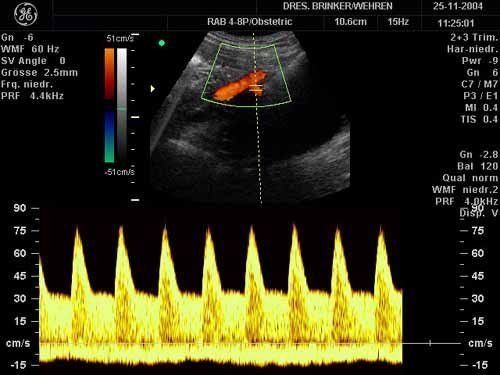

Farbcodierte Doppler-Ultraschalluntersuchung

Mit dieser technisch sehr aufwändigen Untersuchung werden die Blutströme im Körper von Mutter und Kind farblich dargestellt.

Dadurch wird es möglich, eine Minderdurchblutung des Mutterkuchens rechtzeitig zu erkennen, auch die Frühzeichen der sogenannten "Schwangerschaftsvergiftung" oder Gestose können Wochen bis Monate im voraus entdeckt und entsprechende Behandlungsmassnahmen eingeleitet werden.

Beim Kind können die Durchblutung diverser Schlagadern (Nabelschnur, Gehirn, Aorta, Niere) gemessen und Klarheit über seine Kreislaufverhältnisse gewonnen werden.

Die Beurteilung des kindlichen Herzens wird erheblich verfeinert, da die Blutströme durch das Herz in ihrer Richtung verfolgt, Herzfehler somit leichter entdeckt werden können.

Auch die Unterscheidung, ob ein auffallend kleines Kind im Mutterleib nur "zierlich" oder infolge Nährstoffmangels minderwüchsig ist, kann mit dieser Methode getroffen werden.

Sehr wichtig ist diese Untersuchung bei Mehrlingen und wird in diesen Fällen auch von den Gesetzlichen Krankenkassen übernommen.